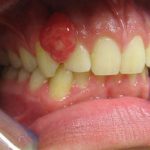

Epulis

A nonspecific word for any inflammatory cellular proliferation or a tumor‐like growth or lump of the gingiva.

A type of tumor of the gums or jaw.

An old term for a swelling of the gum. Such a swelling is usually either a reparative ‘granuloma or consists of a mass of fibrous tissue developed around ill-fitting dentures.

Epulis is a term applied to any tumour connected with the jaws.